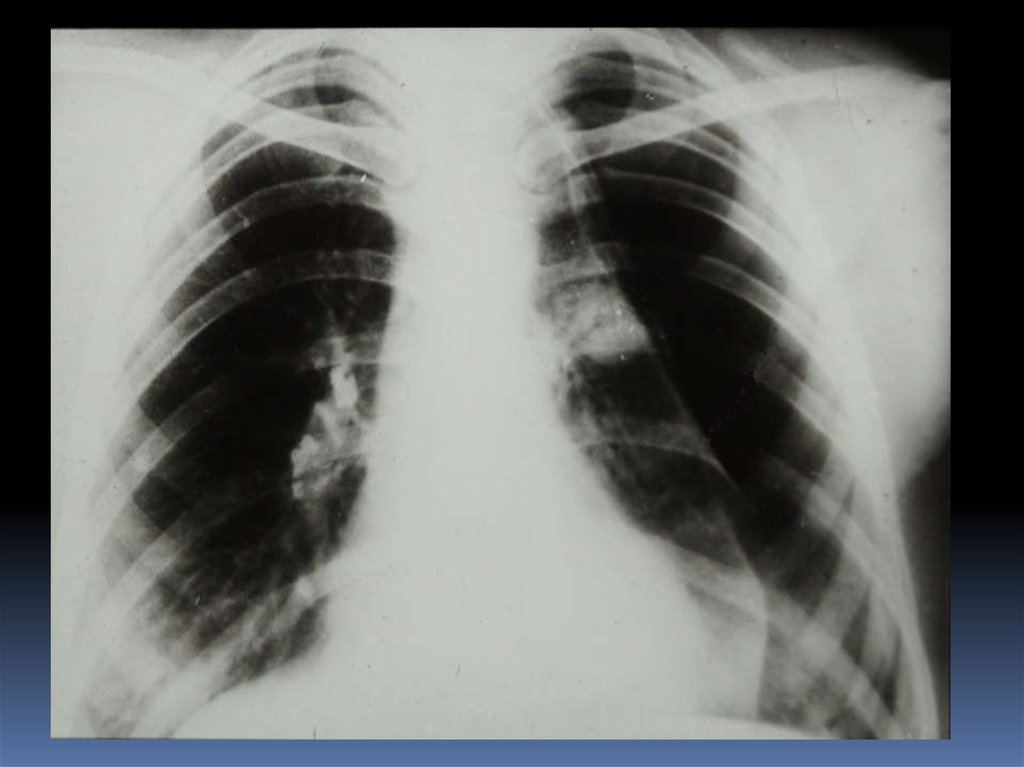

5. Проведение рентгеноскопического исследования раненого.

6. Проведение рентгенографического исследования раненого.

7. Виды травматического повреждения грудной клетки:

пневмоторакс;

гемоторакс;

гемопневмоторакс;

внутрилегочные гематомы;

дисковидные ателектазы;

посттравматические пневмонии.